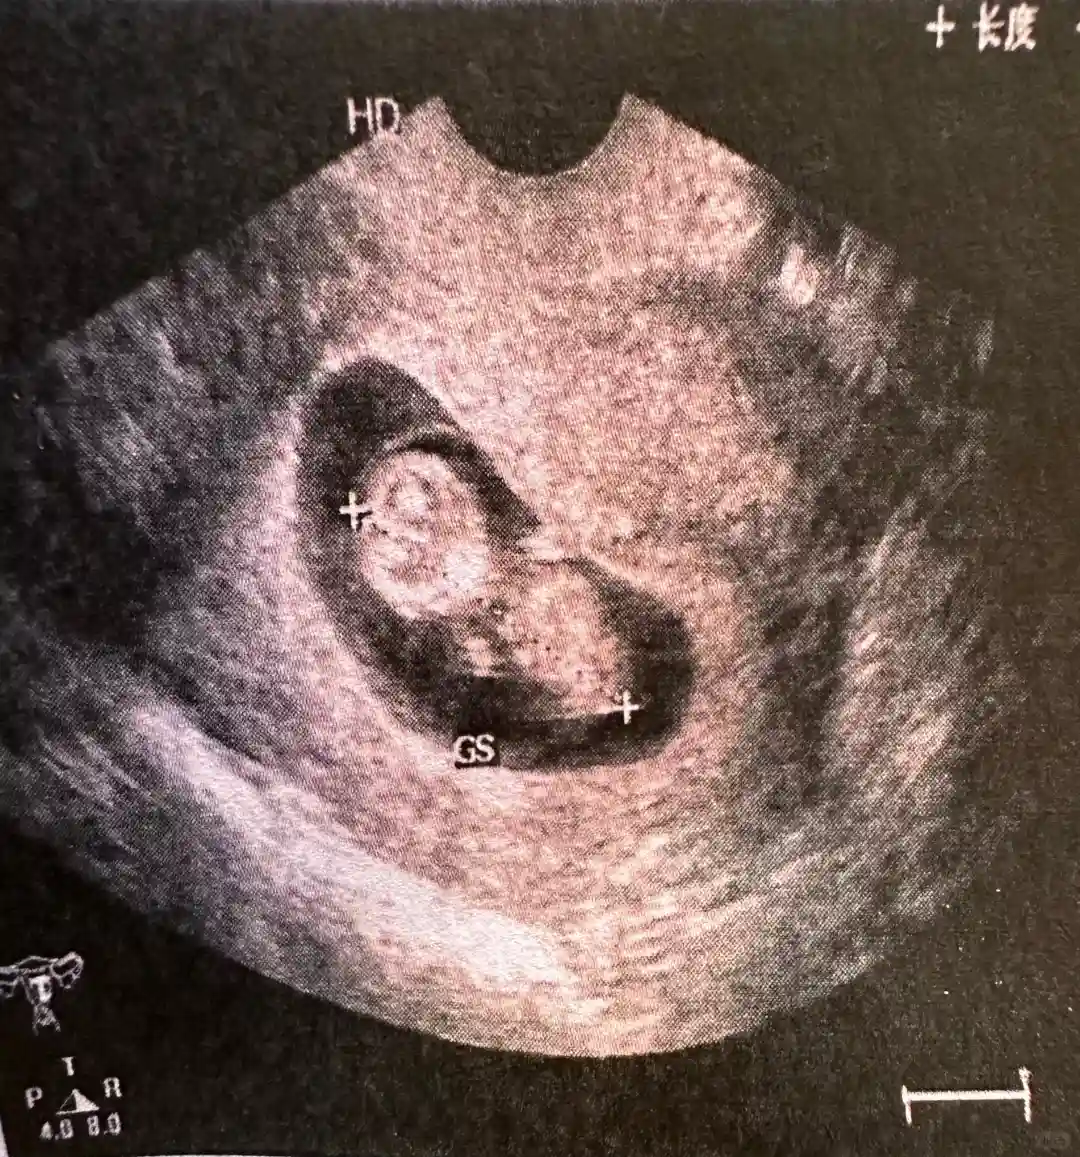

今天10周+4,B超下11周

看到了崽崽的模样

B超医生说他(她)小肚子圆圆的

特别可爱😘😘😘